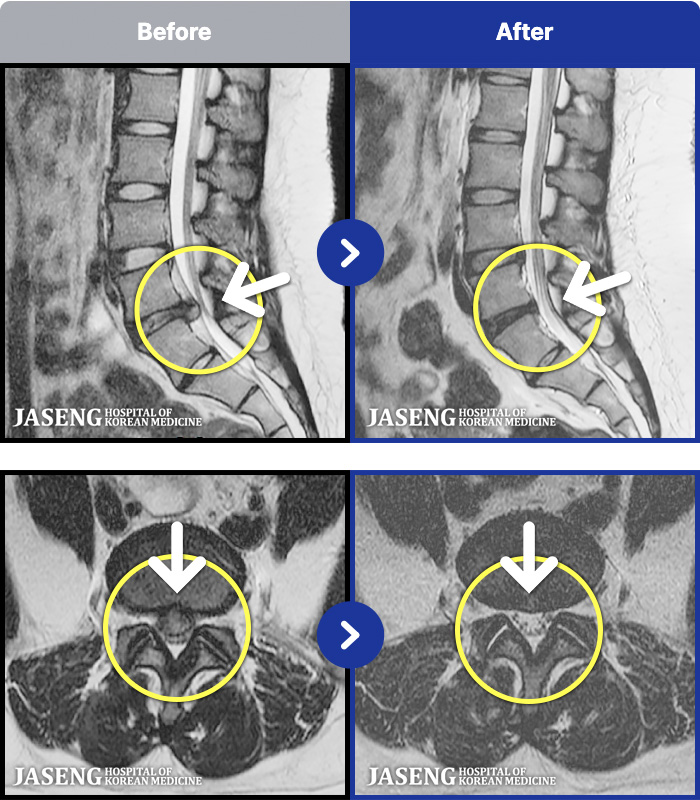

MRI ġ

1,237 MRI ũ ʸ Ȯϼ.